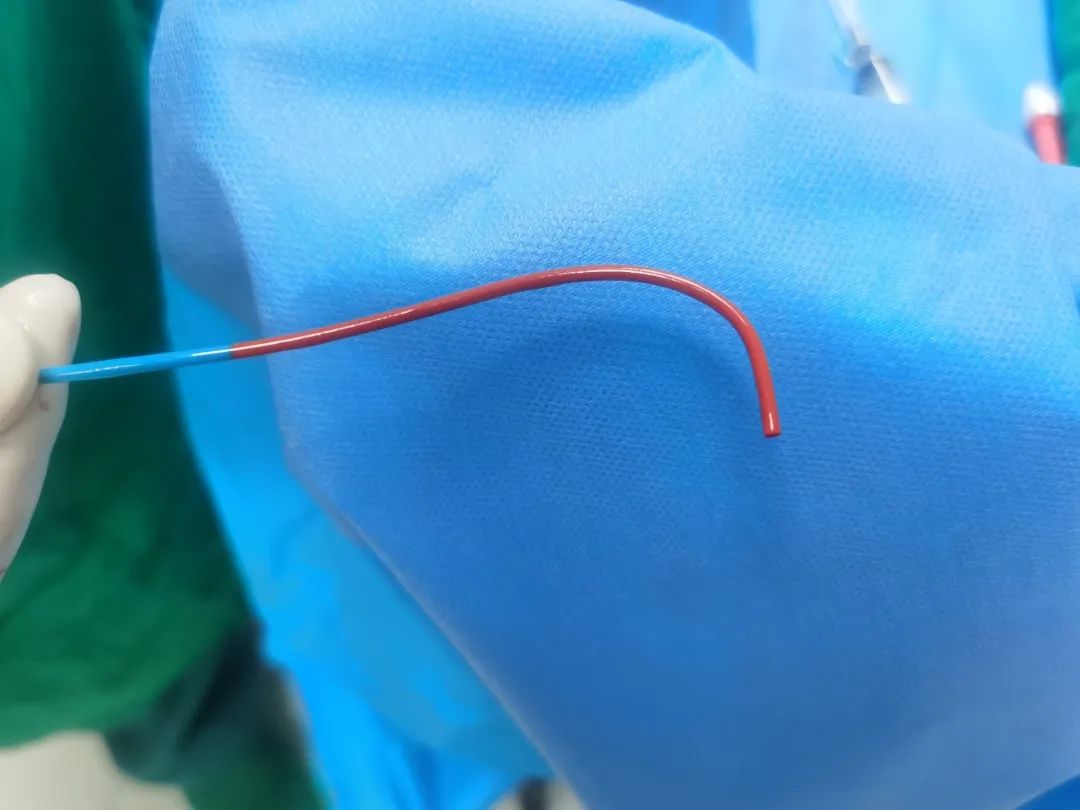

对于部分病例,头端超选比较困难,可以采用头端蒸汽塑形,达到很好的超选目的。